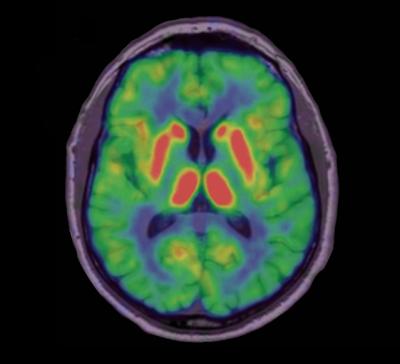

image: This is a PET image of a healthy brain. This image relates to an article that appeared in the June 30, 2010, issue of Science Translational Medicine, published by AAAS. The study, by Dr. Marios Politis of Imperial College London in London, UK, and colleagues, is titled, "Serotonergic Neurons Mediate Dyskinesia Side Effects in Parkinson's Patients with Neural Transplants." view more

Credit: Image courtesy of Marios Politis